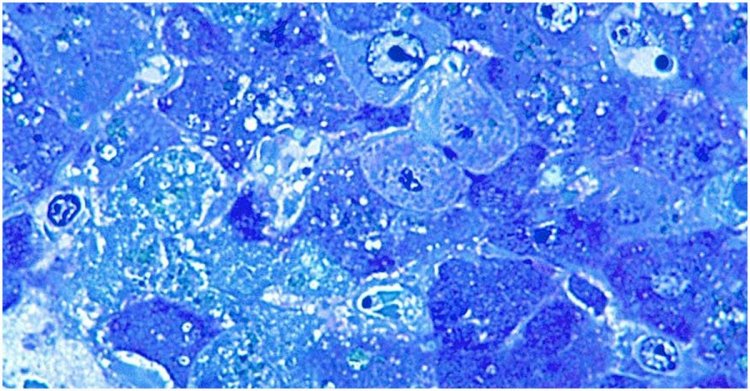

লাসা ভাইরাসের কারণে রক্তক্ষরণজনিত অসুস্থতা তৈরি হয়। এটি ভাইরাসের অ্যারেনাভাইরাস পরিবারের একটি সদস্য।